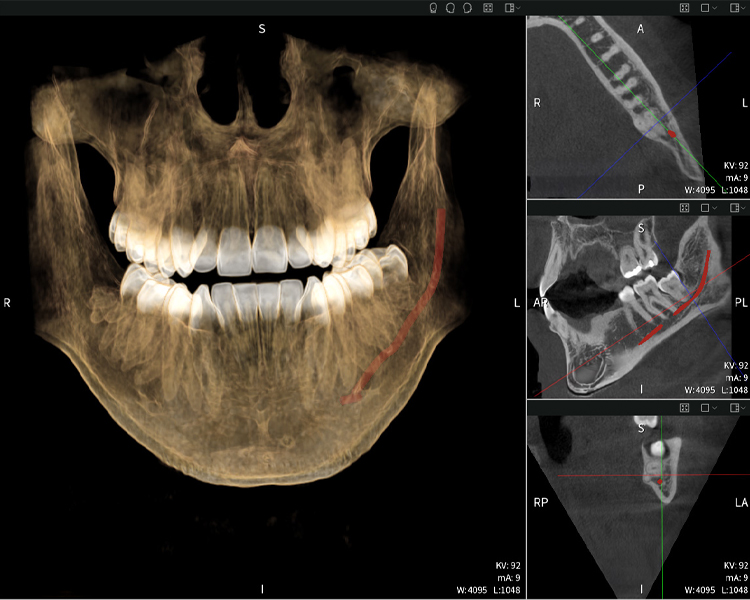

Below you will find a case from Dr. med. dent. Oliver A. Centrella, in which the CBCT images obtained with Seethrough Max provided crucial information on the complex anatomy and the critical relationship between the wisdom teeth and the inferior alveolar nerve. In this case, there is a indication for the surgical removal of the wisdom teeth.

Figures b–d show various views of a 3D reconstruction of the mandible, providing a comprehensive overview of the mandibular anatomy, the position of the nerves in relation to the teeth, and allowing assessment of tooth symmetry and alignment.

Figure d shows the previously treated tooth 48, with its crown removed, and its roots left in proximity to the nerve, illustrating the high risk of nerve damage.

Figure e: The panoramic X-ray serves as an initial assessment tool, showing the general positioning of the teeth as well as any potential pathological changes. Notably, on the right side (tooth 48), the situation following a crown amputation performed by an external practitioner is visible. The two severely curved roots remain in close topographical proximity to the inferior alveolar nerve within the bone. This suggests a deliberate decision to avoid the increased risk of nerve injury during a complete extraction, and represents a clinically relevant finding. In summary, CBCT scans with Seethrough Max, provide crucial information about the complex anatomy and the critical relationship between the wisdom teeth and the inferior alveolar nerve. This detailed preoperative diagnostic imaging is essential for safe and successful surgical procedures in the mandibular region.